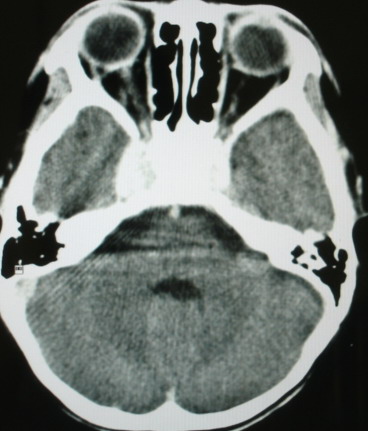

m/8y/,右侧眼睑下垂数日,发育良好,无外伤史,无头痛、恶心、呕吐,学习成绩良好。

ct意见:1、颅内血管畸形。2、右侧海绵窦血管瘤(颈内动脉海绵窦段动脉瘤)。3、脑萎缩。4、建议mr或dsa.

增强片